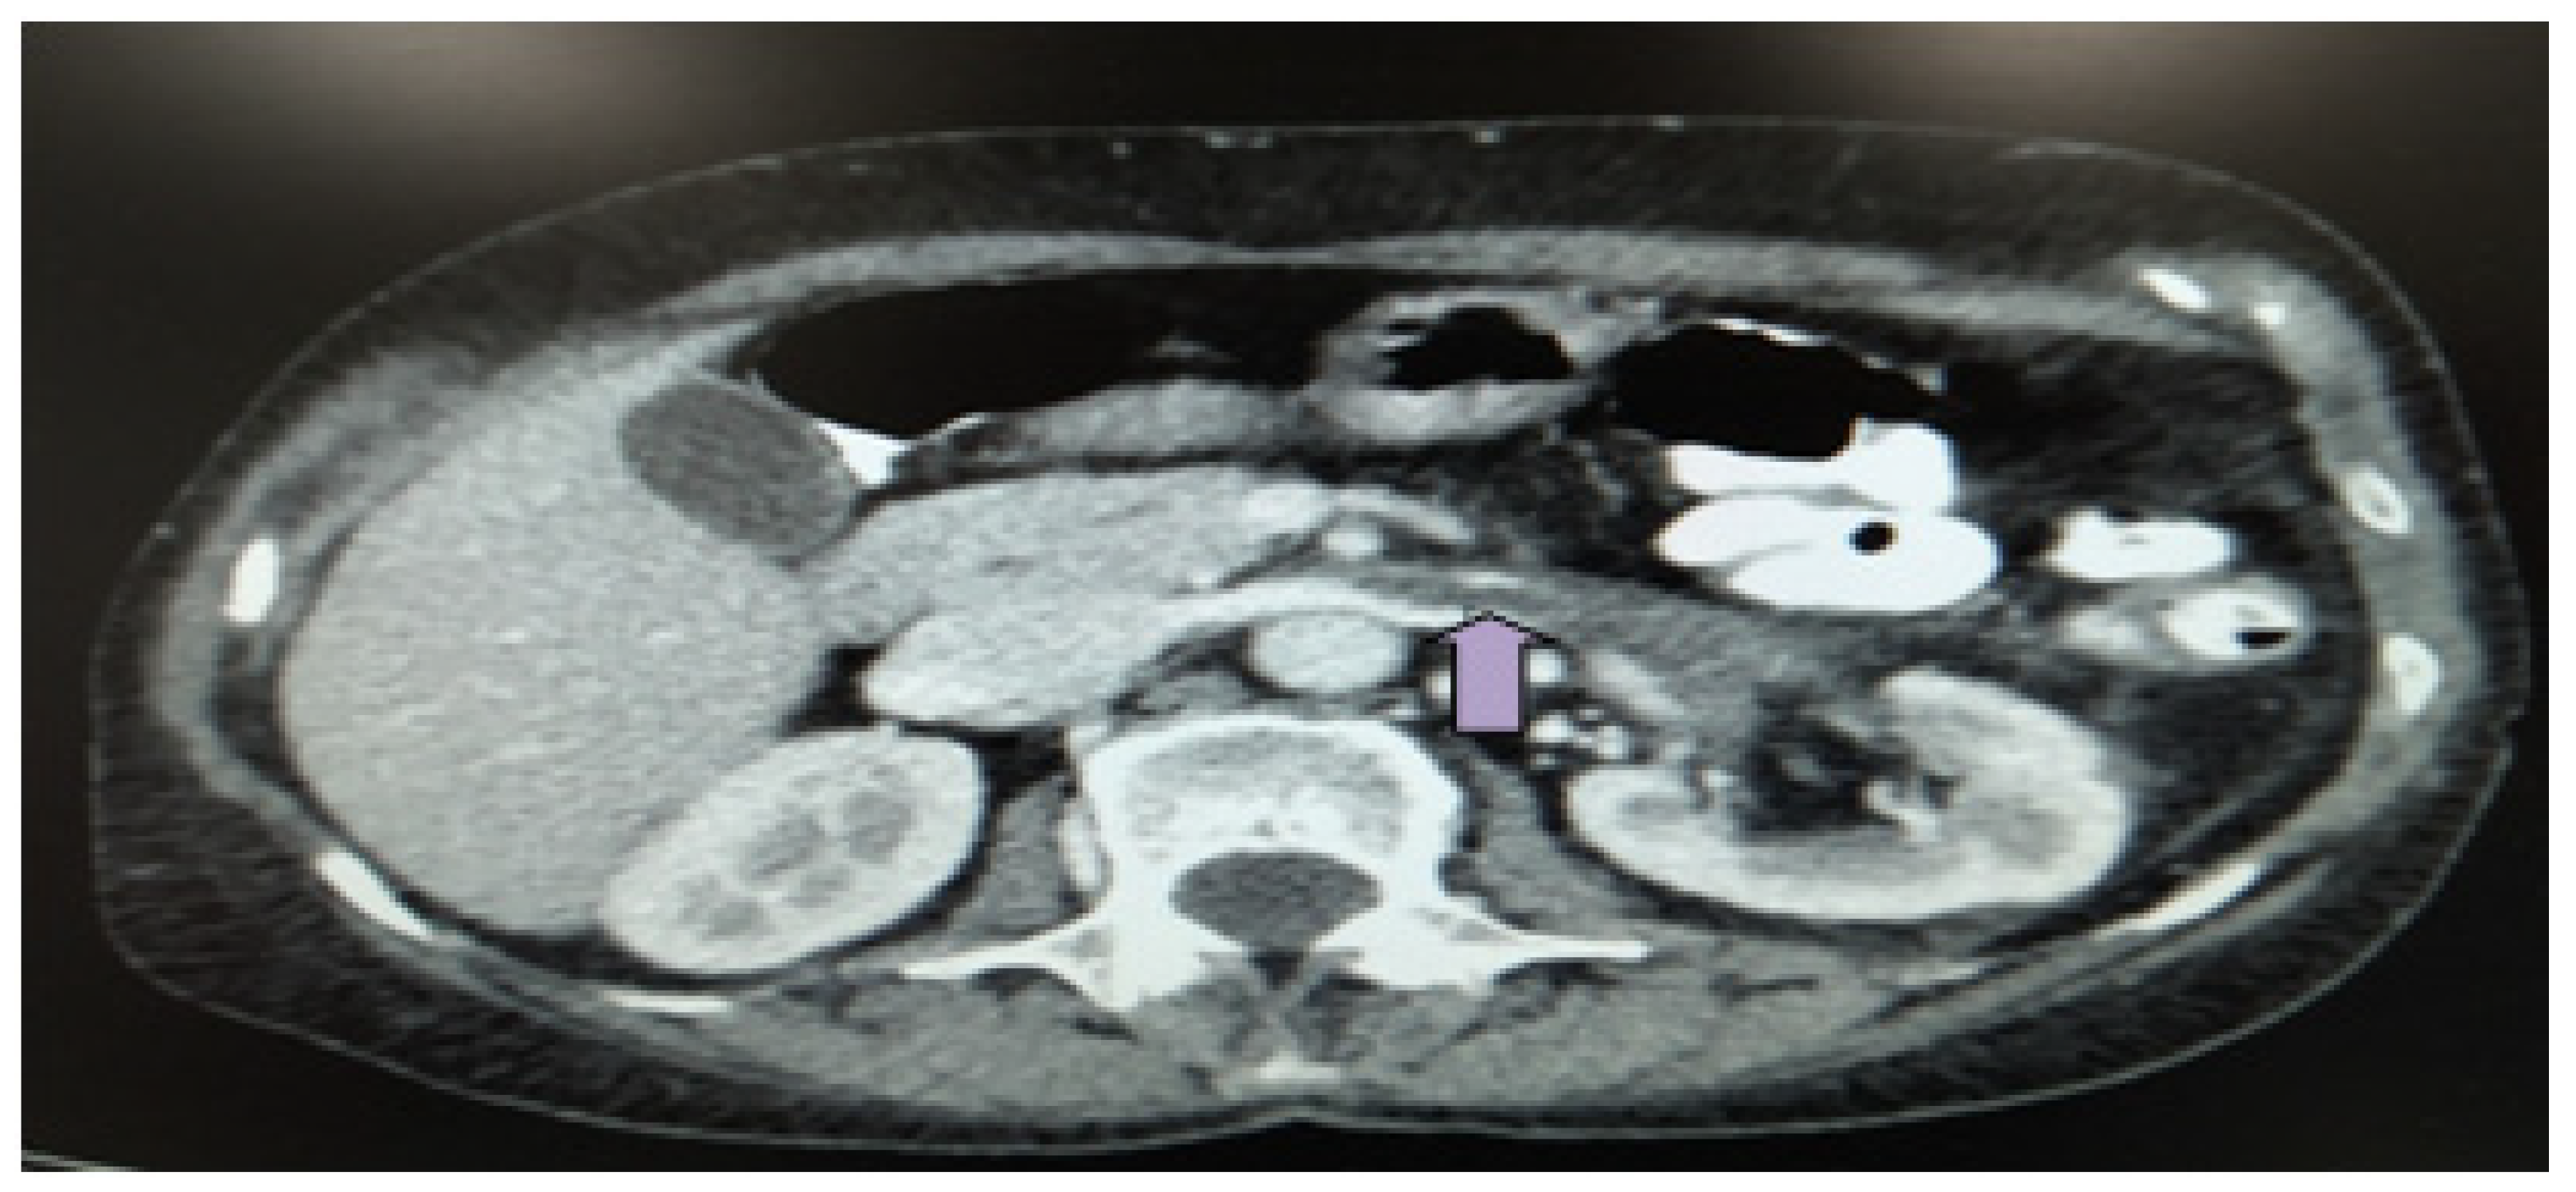

Figure 3 CT scan showing left renal artery thrombosis (white asterisk

CT image of subocclusive thrombus of right renal artery (right arrow Case Report Renal Artery Thrombosis  To the best of our knowledge this. Web in this case report, the authors review a case of renal infarction caused by renal artery thrombosis in a patient with risk factors for. Web  in this case report, the authors review a case of renal infarction caused by renal artery thrombosis in a patient with risk. Case Report Renal Artery Thrombosis.